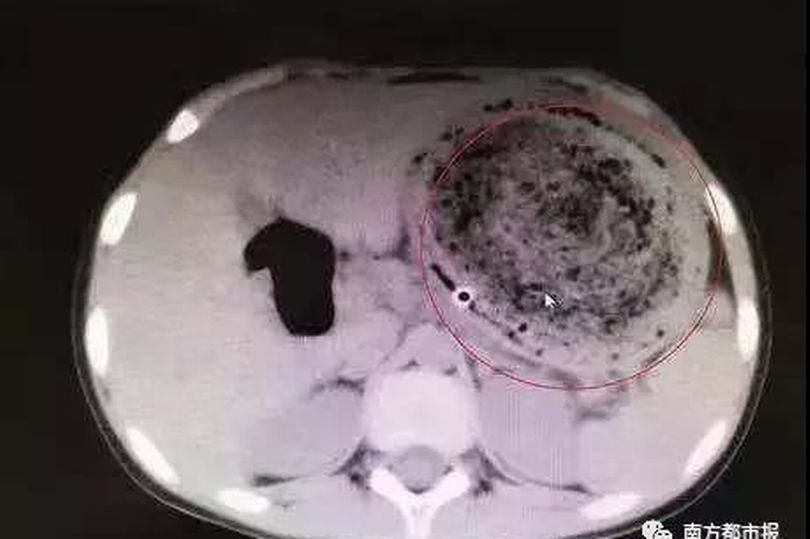

Bác sĩ đã rất ngạc nhiên khi chụp CT và phát hiện một búi tóc khổng lồ lẫn với cặn thức ăn. Tuy nhiên, búi tóc to bằng quả bóng này không thể được loại bỏ thông qua nội soi vì có dấu hiệu vôi hóa.

Hình ảnh búi tóc rối trong dạ dày của Phi Phi.